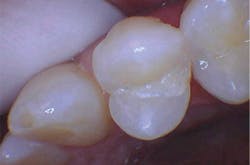

The removal of dental hard tissue is accomplished by what is known as thermomechanical photon-induced water-mediated ablation, which is a process in which the micro-explosive force of photons on water droplets results in the selective removal of carious dentin (figures 2a–2d). The laser energy seeks out tissue with higher water content, such as a carious lesion, and evaporates it without contact, vibration, or the introduction of microfractures, leaving the surrounding healthy enamel and dentin intact.

Figures 2a–2d: A Class II posterior cavity preparation